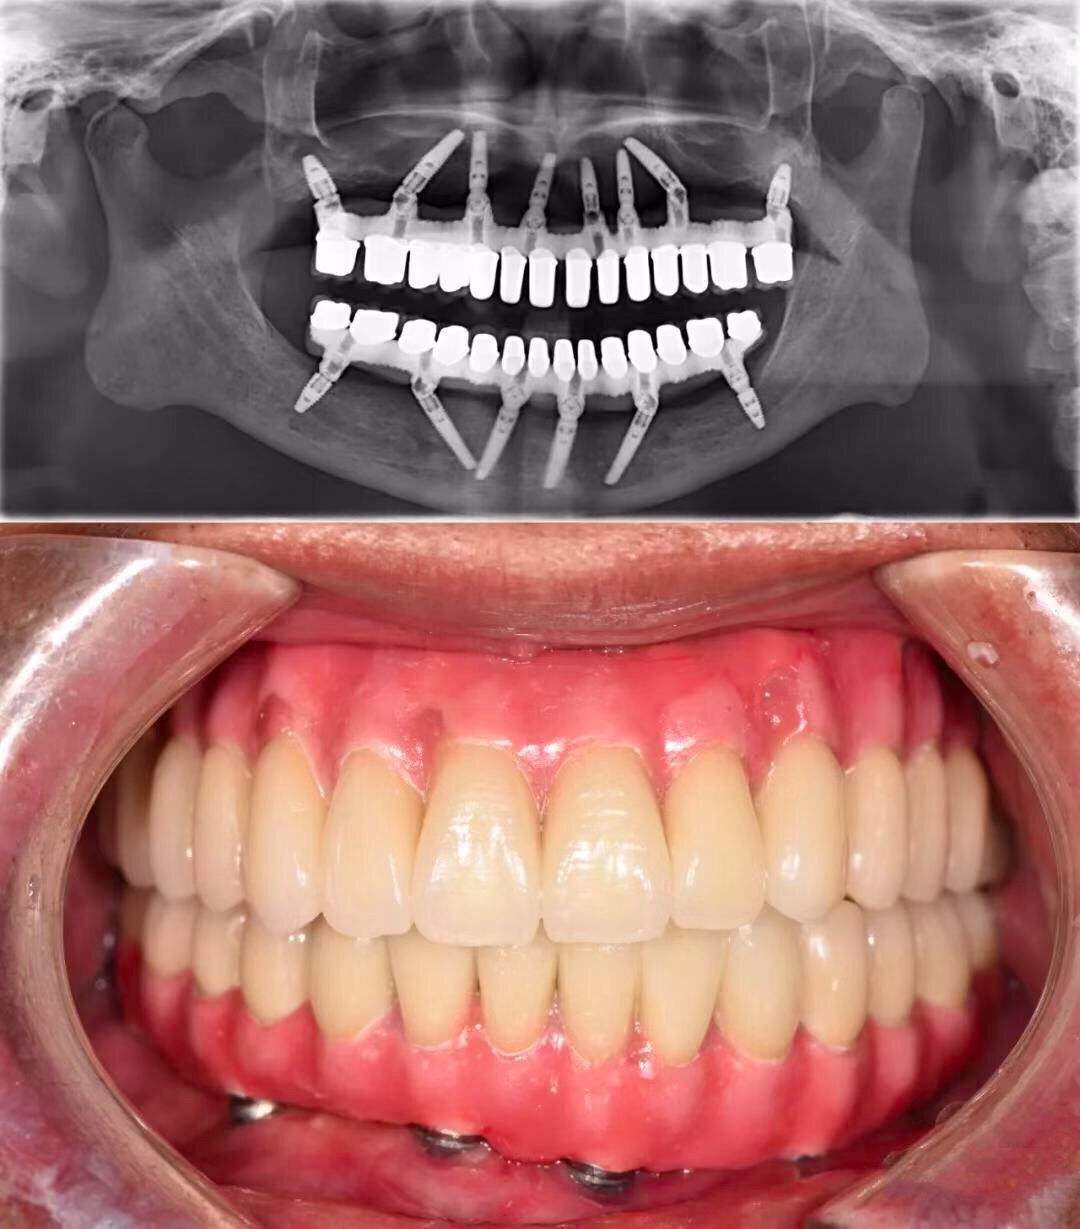

口腔种植效果怎么样 术前准备很关键

口腔种植是生活中非常常见的一种口腔修复手术,随着医学不断发展进步,口腔种植的方法也越来越多,且效果也越来越好,虽然一般口腔种植的效果是比较好的,但是术前准备工作也是很重要的,各位千万不可大意,下面我们具体了解一下具体要准备哪些术前准备。